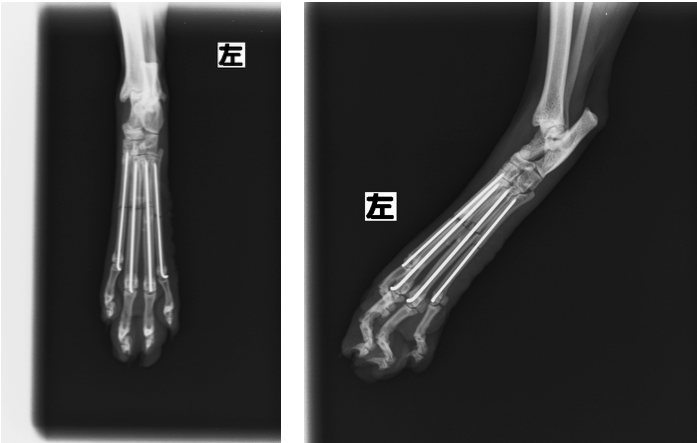

【術後レントゲン写真】

各骨折片は良好に整復されている